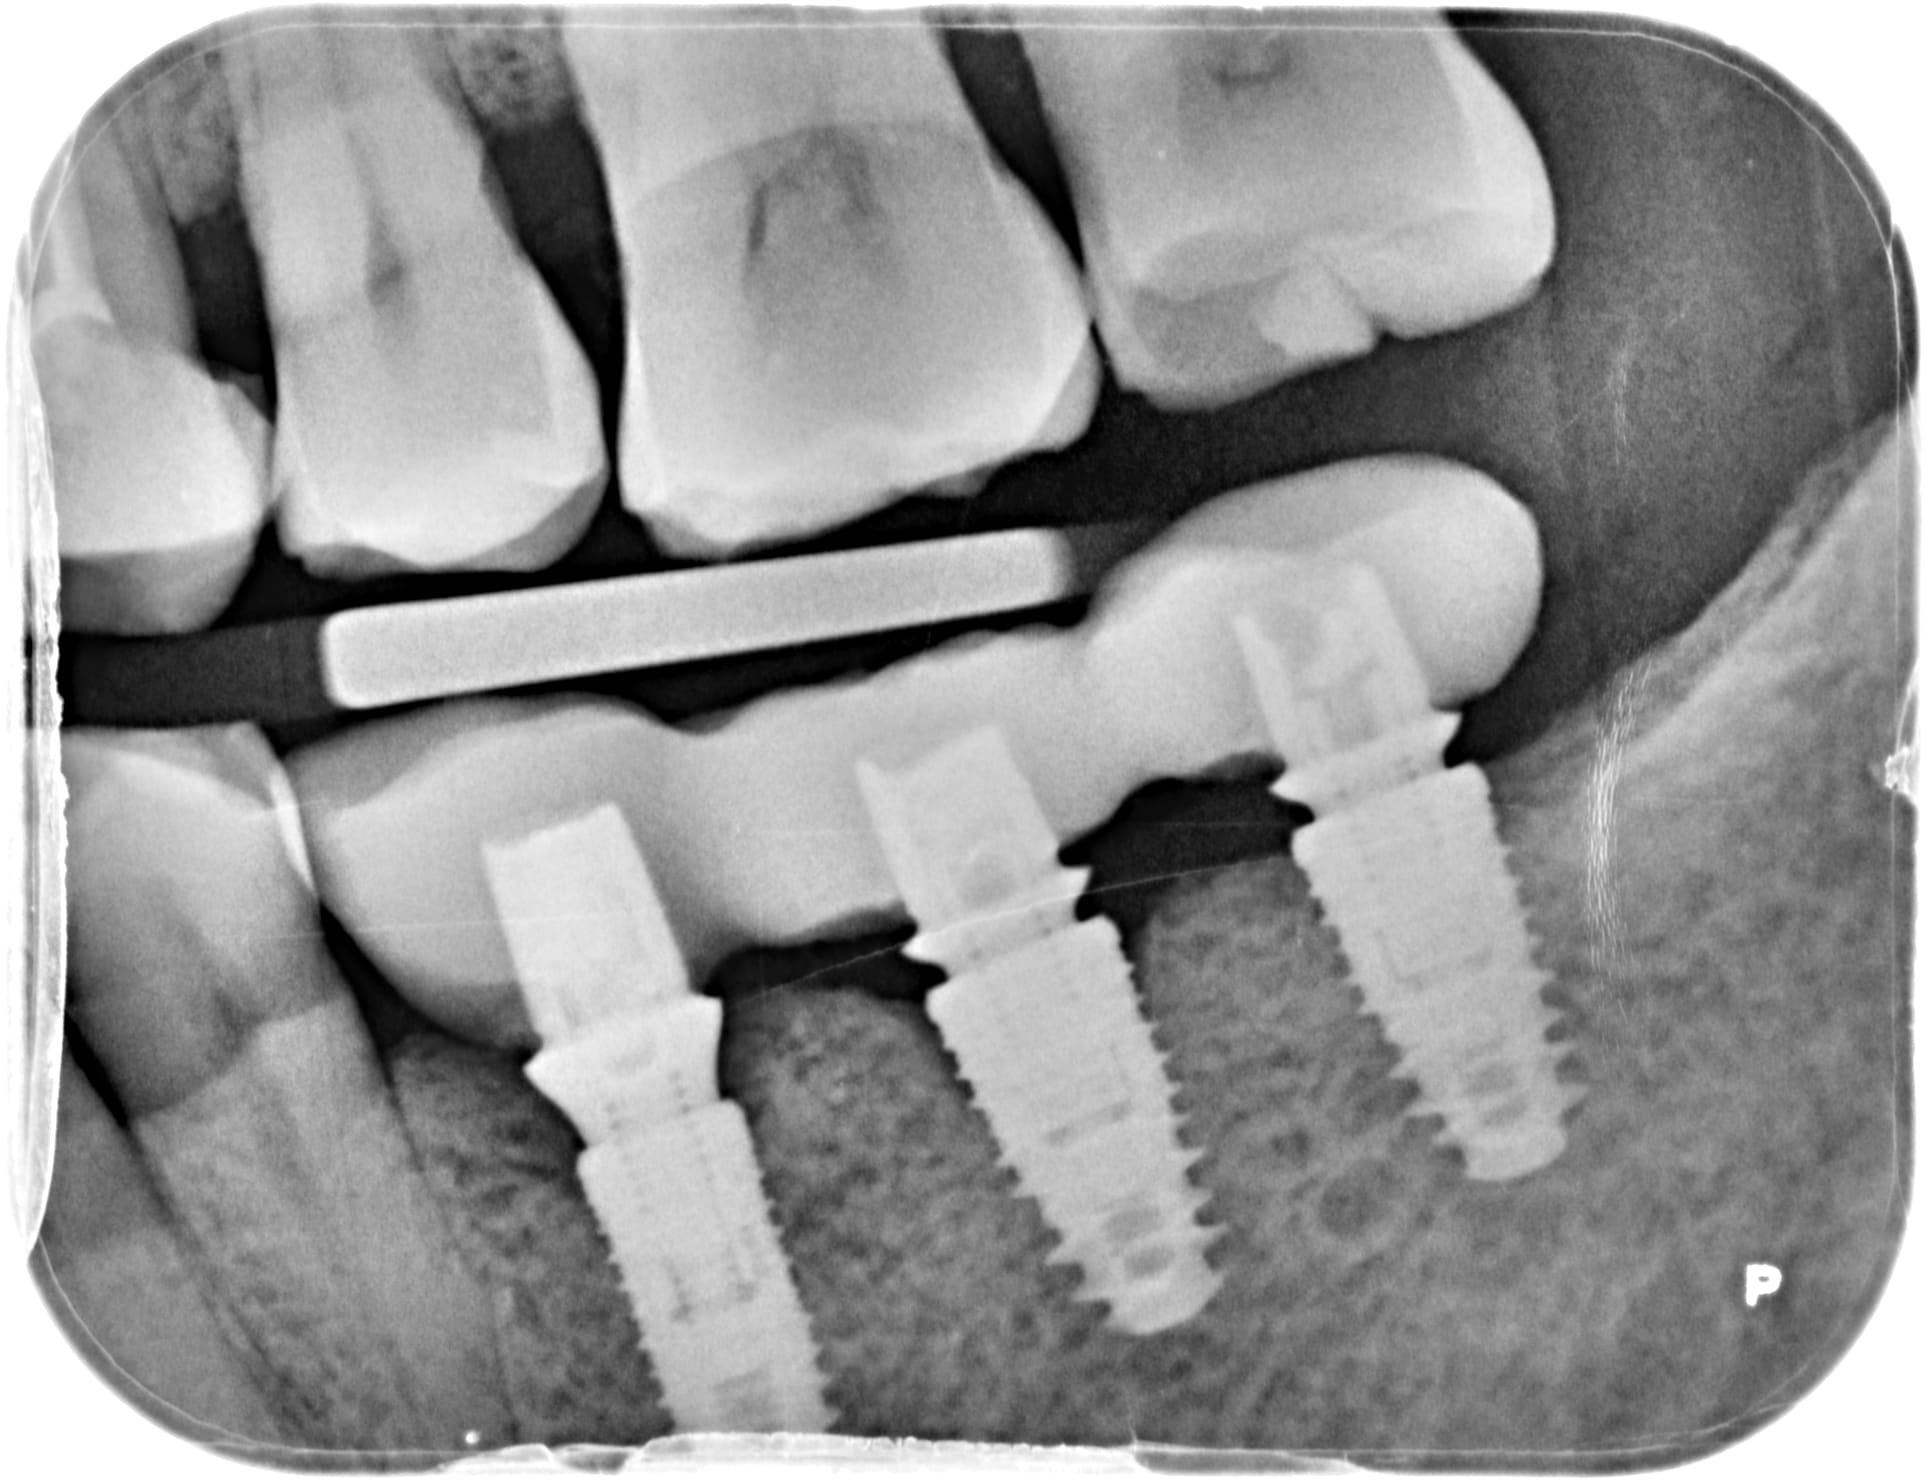

Kontact Biotech....;-) 100% sûr...

https://www.biotech-dental.com/professionnel-sante/solutions-dentaires-produits/implant-dentaire/kontact/